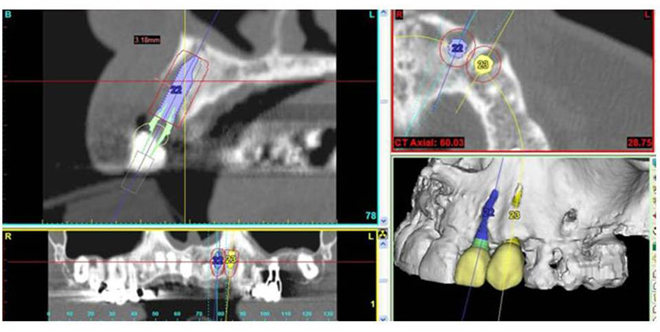

Computer-assisted implantology is performed using a computerized tomography (CBCT Scan) of the patient’s maxilla and mandible. This Scan constitutes an exact replica of the patient’s bone architecture in 3D images and according to which we develop the plans and specifications for the surgery.

Thanks to this advanced technology, the dental surgeon can establish the diagnosis with great precision and plan his cases in 3D (dimensions) of space even before performing the surgical procedure.

1. – A CBCT-Scan provides a detailed image of the bone architecture revealing the quantity and quality of the patient’s jawbone in 3D.

2. – The simulation of the case from the data of the Scan which is recorded in an interactive software allows the dentist to evaluate the patient’s anatomy and to simulate the positioning of the implants, as well as the bone augmentation when a graft is required.